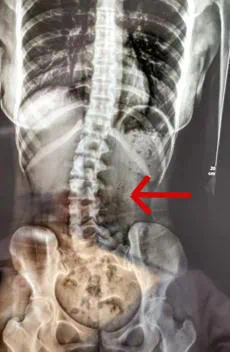

“侧卧睡、一条腿伸直,另一条腿弯曲搭过来”……这是不少人日常睡姿。不过很少有人知道,长期这种睡姿可能会导致脊椎出问题。广州医科大学附属第三医院就曾在微信公号分享过一个患者案例:“18岁的女生小邹(化名),经常出现腰痛、脖子酸等症状,并且情况逐渐严重。于是到医院就诊,医生检查发现脊柱严重侧弯,经过x光检查,发现她的腰椎向右侧弯、旋转,并以腰2椎体为中心向右侧弯,脊柱向右发生明显侧弯。”医生最后发现竟是因为她的睡眠姿势引起,小邹长时间习惯侧躺一边睡,并且腿的摆姿不正确。“原有正常的脊柱体态在日积月累的错误睡姿中逐渐失衡,骨盆与脊柱位置变化,脊柱就发生了侧弯。”广州医科大学附属第三医院中医科主任医师胥海斌介绍。胥海斌医生介绍,这种睡姿除了会导致脊柱侧弯,长期还可能会导致腰椎间盘突出。这种睡姿往往会导致脊柱在很长的一段时间里都处于“旋转”的状态,使得相邻椎间盘之间所产生的压力增加,可能会致使脊柱的髓核向某个方向隆起直至突出,使神经根受压,从而诱发腰椎间盘突出症。①我们从小就被家长和老师教育,“坐有坐相,要挺胸抬头坐好了。”北京协和医院康复医学科副主任康复师袁望舒2019年曾在健康时报刊文中表示,其实挺胸抬头并不是最正确的姿势。袁望舒医生介绍,从侧面看,脊柱是存在着四个生理曲度的,胸椎本来就是后凸的,过分挺胸反倒会减少了正常的生理曲度。有的人不是驼背,而是平背,这样就更不应该挺胸了。②究竟怎样坐才是正确的呢?你认为下图中正确的坐姿是几号?